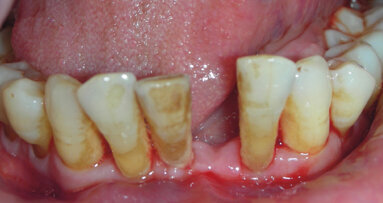

Il paziente F.C., di anni 75, si presenta alla mia osservazione lamentando mobilità della protesi scheletrata inferiore. All’esame clinico si evidenzia una non congruità della stessa e un elevato grado di mobilità degli elementi dentari residui 4.4, 3.4, 3.5. L’elemento 3.3 ha invece grado di mobilità zero. L’ortopantomografia effettuata pochi mesi prima dal paziente conferma la diagnosi clinica di malattia parodontale sugli elementi dentari residui, oltre alla presenza di trattamenti canalari incongrui e processi cariosi diffusi (Fig. 1).

Il primo prevede le estrazioni degli elementi dentari residui e la fabbricazione di una protesi totale inferiore; il secondo consiste invece nel posizionamento di quattro impianti interforaminali e la successiva consegna di una protesi totale inferiore su barra. Il paziente, informato dei rischi e dei benefici delle due opzioni, sceglie la soluzione implantare. Pochi giorni prima dell’intervento il paziente viene preparato da un punto di vista parodontale sottoponendolo a sedute di igiene orale, curettaggi, istruzione e motivazione all’igiene orale, al fine di poter eseguire la chirurgia implantare in un contesto di tessuti parodontali il più possibile disinfiammati. Alla rivalutazione si osserva un netto miglioramento della situazione parodontale, seppure permanendo l’alto grado di mobilità degli elementi 4.4, 3.4, 3.5 (Figg. 2, 3).